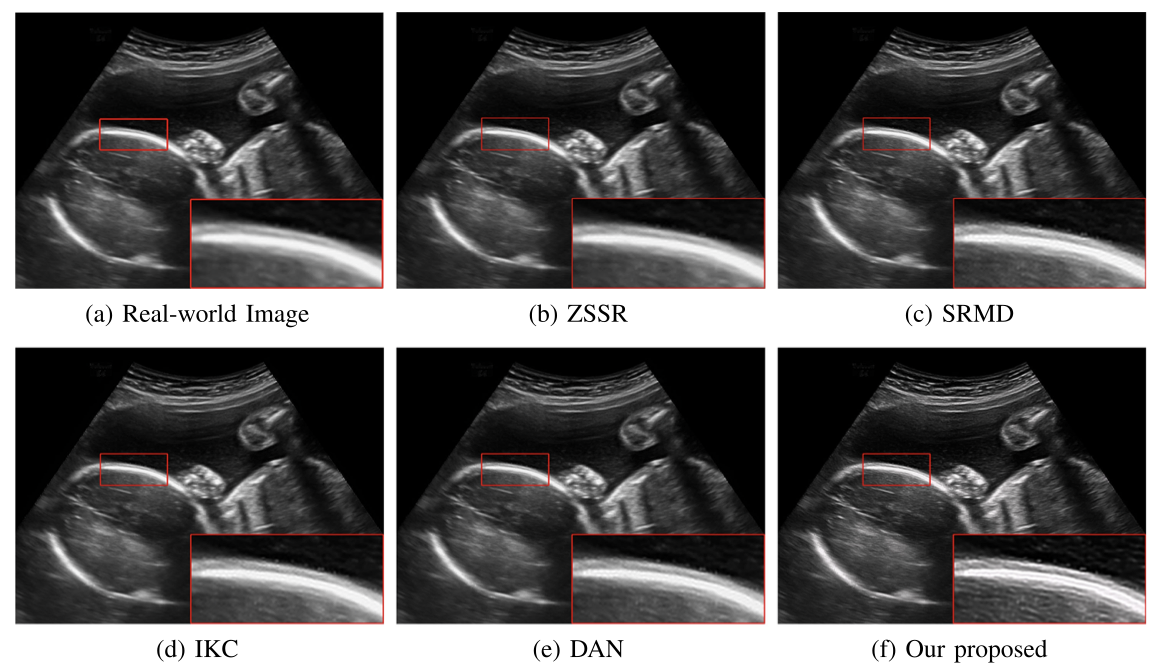

对于超声临床诊断而言,超声影像超分辨(ultrasound image super-resolution)可以提高超声成像质量,从而提高疾病诊断的准确性。但由于传感设备和传输介质的差异,实际场景中超声成像其退化模糊过程是未知且不可控的。为了解决未知退化场景超声医学影像准确超分辨的难题,团队提出了一种有效的基于退化模糊自估计且结合渐进残差学习和记忆提升机制的超声影像盲超分方法,初步实现了真实场景超声影像准确超分辨。相关研究成果发表在人工智能、计算机医学信息交叉领域一区TOP期刊《IEEE Journal of Biomedical and Health Informatics》(IF: 7.7)。公司为论文第一完成单位,太阳成集团tyc539刘恒教授、硕士生刘建勇分别为论文第一、第二作者。

(真实场景超声影像盲超分效果对比图)